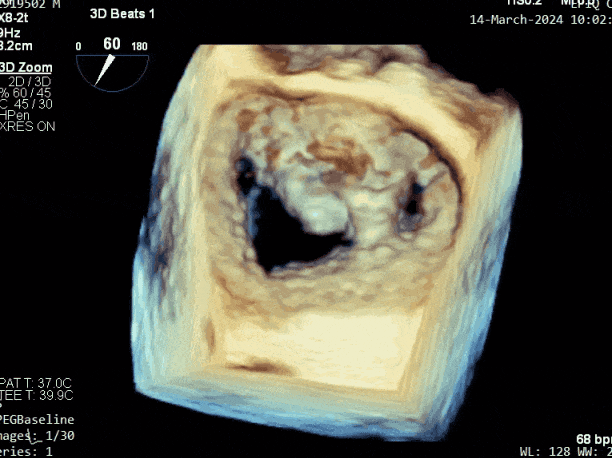

二尖瓣后叶活动受限,呈房源性栓系,以P3区为重,二尖瓣前叶假性脱垂,二尖瓣瓣环前后径49mm,左右径40mm。

第三个瓣膜夹释放后评估,释放后评估,二尖瓣呈双孔,组织桥张力合适,瓣膜夹轴向与二尖瓣闭合线垂直,无残余反流

2. 本例患者外院超声心动图考虑二尖瓣前叶脱垂,入院后经食道超声心动图明确该患者为二尖瓣后叶活动受限,呈房源性栓系,二尖瓣前叶假性脱垂,超声特征表现为心房功能性二尖瓣反流终末期,呈现出很典型的二尖瓣后瓣环向左室游离壁顶部位移和后叶挛缩表现,同时合并有明显的二尖瓣瓣环扩张、圆形化,左房增大等不利因素,术中通过精准的影像指导和手术操作,成功行TEER,二尖瓣反流程度减轻至微量。